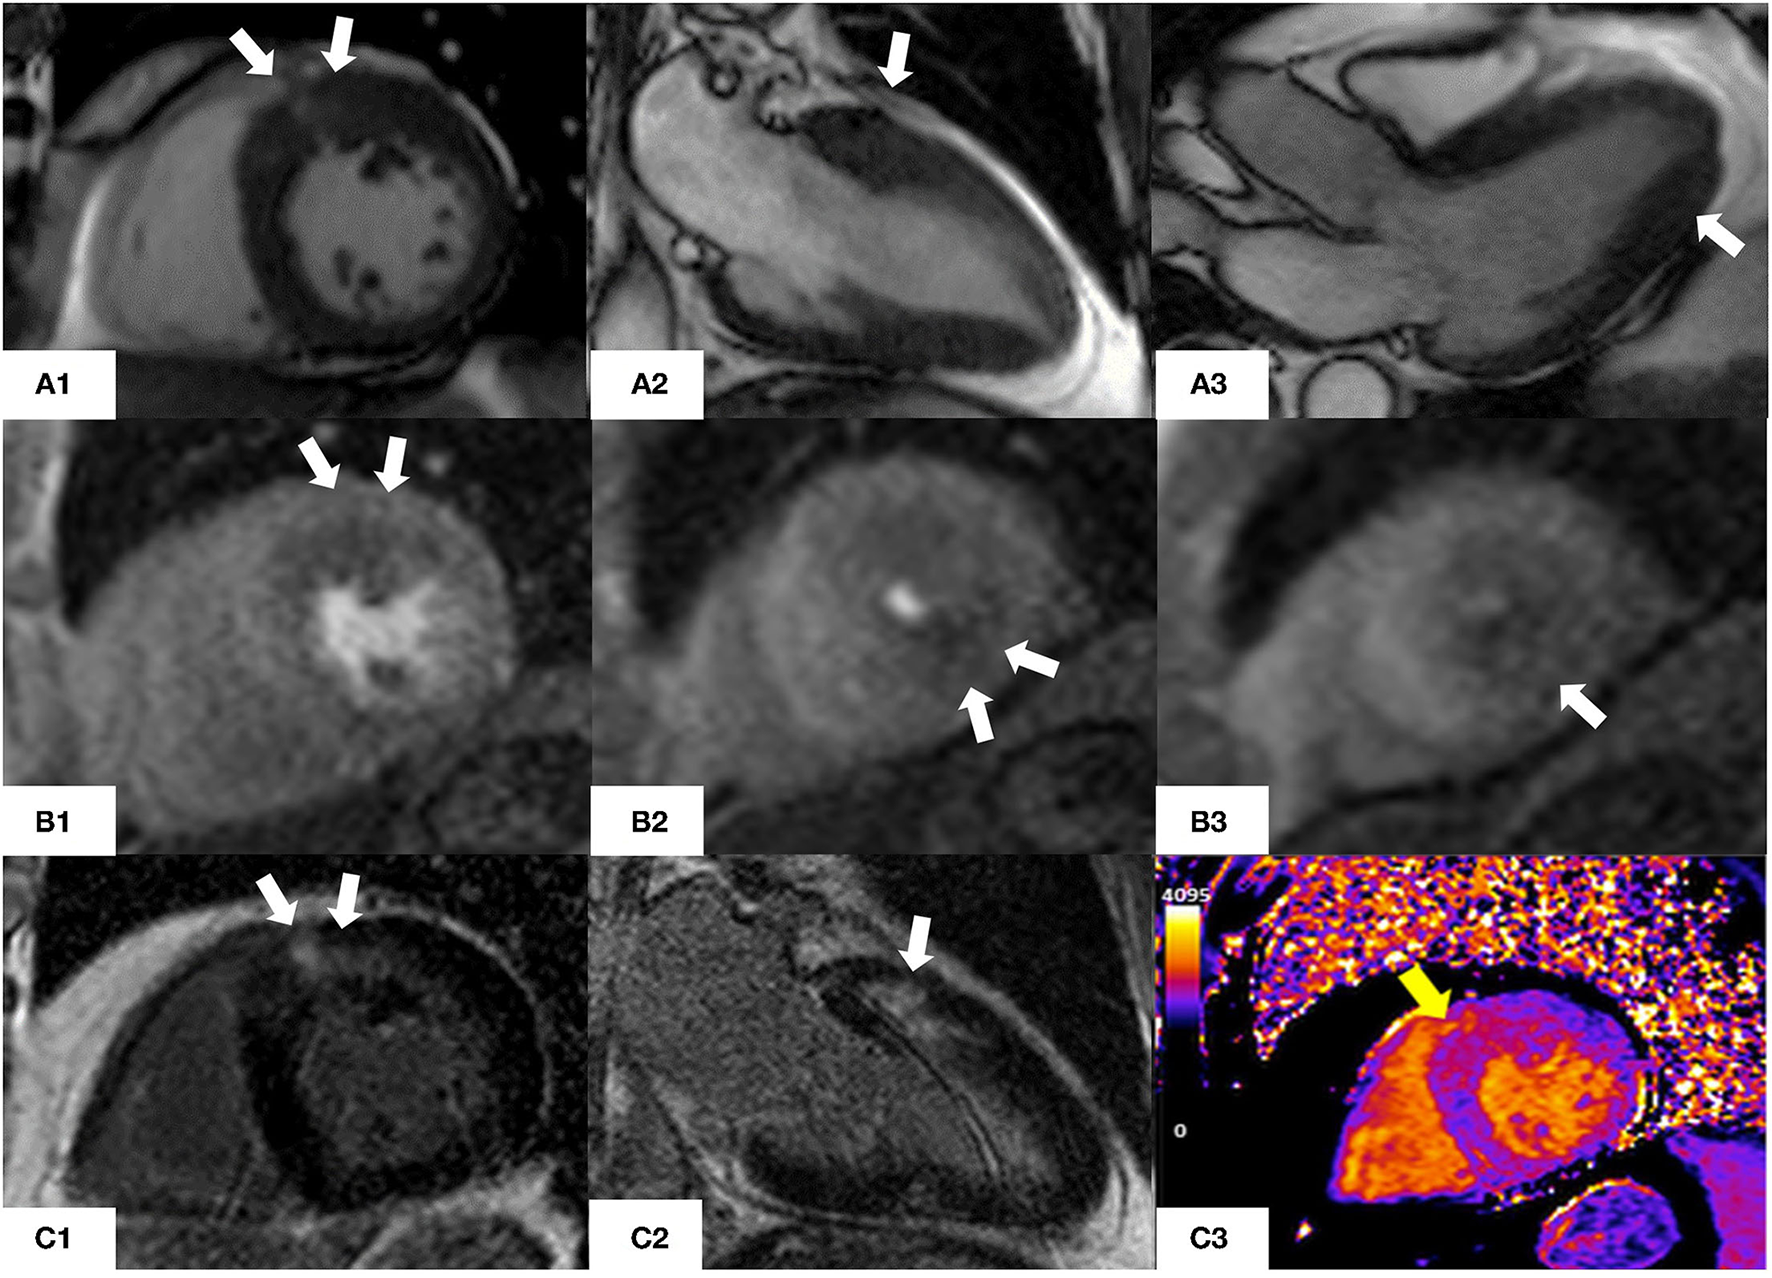

Figure 4 shows CMR findings in a patient presenting with angina and mild increase in the levels of troponin T.

Figure 4

CMR findings in a 76 year old man with asymmetric hypertrophic cardiomyopathy who presented with atypical chest pain and non-sustained ventricular tachycardia on a recent ECG-Holter. (A1–A3) Steady-state free precession sequence (SSFP) cine imaging showing asymmetrical hypertrophy of the basal anterior wall and mild apical hypertrophy (white arrows). (B1–B3) Stress perfusion images showing inducible microvascular dysfunction of the hypertrophic basal anterior wall and mid-cavity and apical inferior wall (white arrows). (C1, C2) Late gadolinium enhancement imaging (LGE) showing patchy myocardial fibrosis of the hypertrophied segments (white arrows). (C3) Native T1 mapping (basal short axis view). Increased native T1 values (yellow arrow) in the basal anterior and basal anteroseptal walls (1,170 msec, normal range 1,000 ± 50 msec) matching the patchy LGE noted in panels (C1, C2).